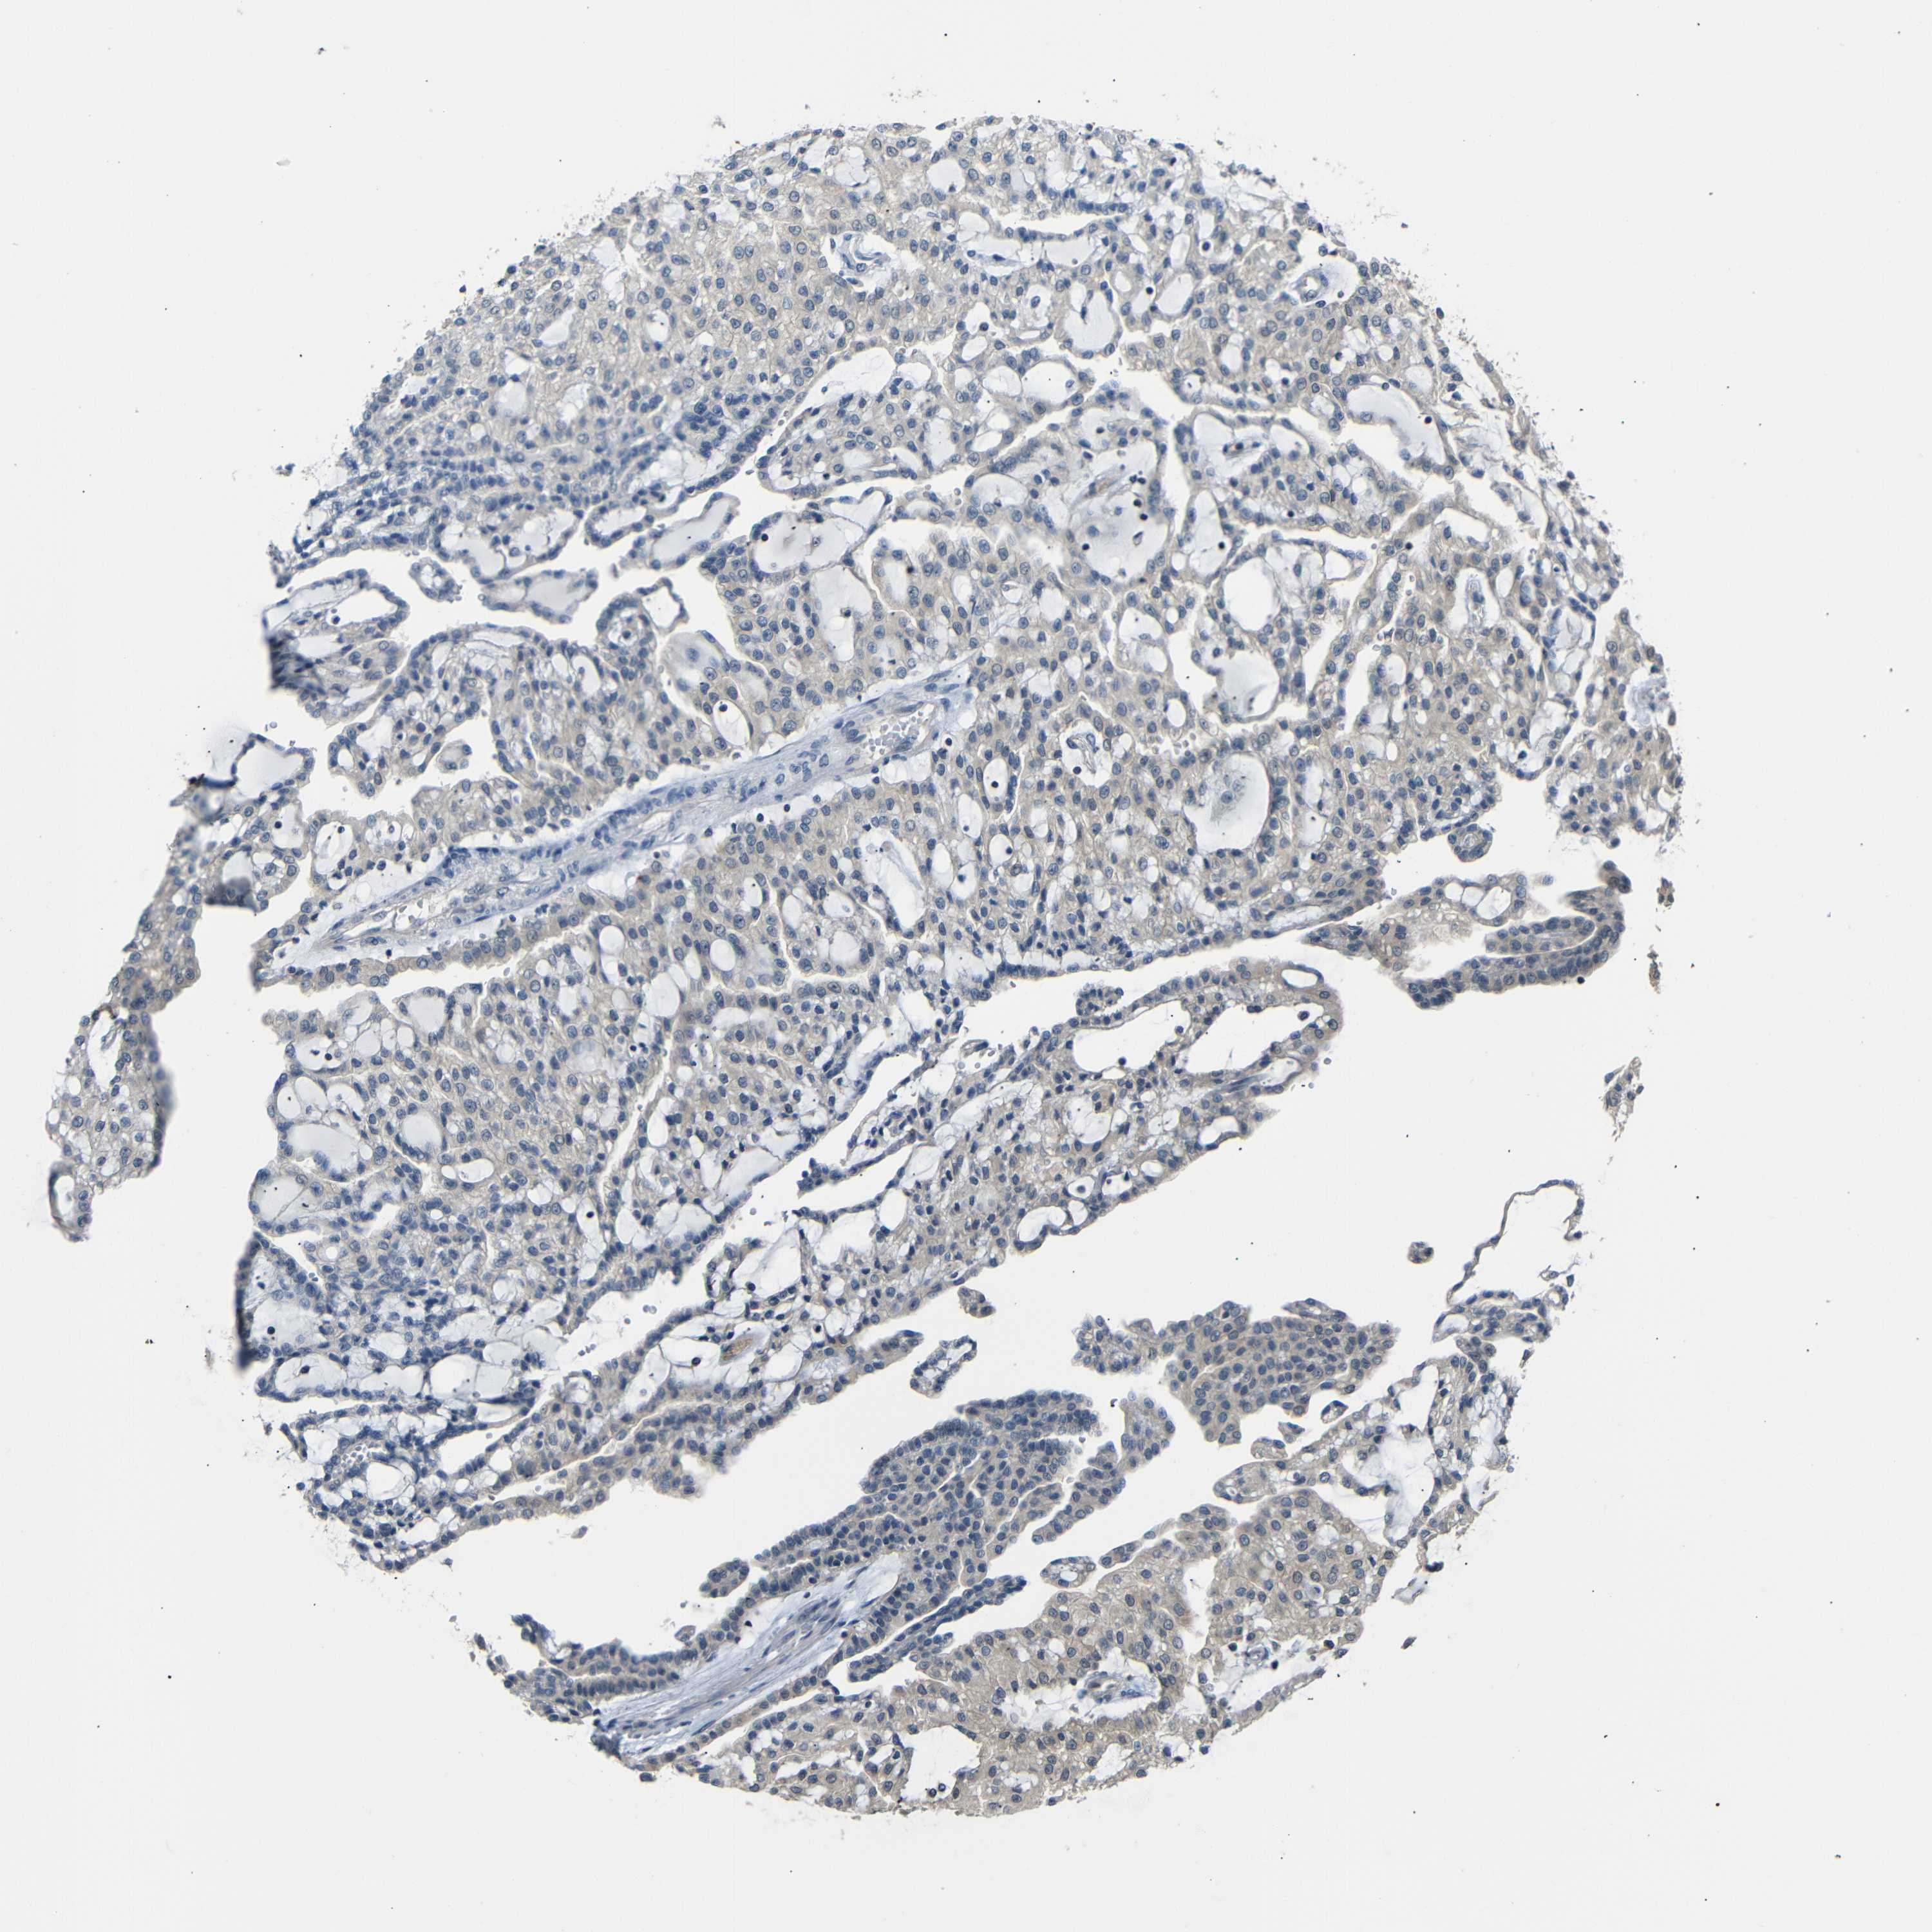

KIDNEY RENAL CLEAR CELL CARCINOMA (TCGA) - Interactive survival scatter ploti

The Survival Scatter plot shows the clinical status (i.e. dead or alive) for all individuals in the patient cohort, based on the same data that underlies the corresponding Kaplan-Meier plots. Patients that are alive at last time for follow-up are shown in blue and patients who have died during the study are shown in red.

The x-axis shows the expression levels (FPKM) of the investigated gene in the tumor tissue at the time of diagnosis. The y-axis shows the follow-up time after diagnosis (years). Both axes are complimented with kernel density curves demonstrating the data density over the axes. The top density plot shows the expression levels (FPKM) distribution among dead (red) and alive patients (blue). The right density plot shows the data density of the survived years of dead patients with high and low expression levels respectively, stratified using the cutoff indicated by the vertical dashed line through the Survival Scatter plot. This cutoff is automatically defined based on the FPKM cutoff that minimizes the p-score. The cutoff can be changed by dragging the vertical line or by entering a cutoff value in the square labeled "Current cut-off".

Under the Survival Scatter plot the p-score landscape (black curve; left axis) is shown together with dead median separation (red curve; right axis). Dead median separation is the difference in median mRNA expression between patients who have died with high and low expression, respectively. It is calculated as follows: median FPKM expression of dead patients with high expression - median FPKM expression of dead patients with low expression. This is intended to aid the user in visually exploring custom cutoffs and the associated p-scores and dead median separation.

Individual patient data is displayed and can be filtered by clicking on one or more of the category buttons on the top of the page. Categories describing expression level and patient information include: high, low, alive, dead, female, male and tumor stages. The scale of the x-axis can be toggled between linear and log-scale by clicking on the "x log" button. Mouse-over function shows TCGA ID, patient information and mRNA expression (FPKM) for each patient.

& Survival analysisi

Kaplan-Meier plots summarize results from analysis of correlation between mRNA expression level and patient survival. Patients were divided based on level of expression into one of the two groups "low" (under cut off) or "high" (over cut off). X-axis shows time for survival (years) and y-axis shows the probability of survival, where 1.0 corresponds to 100 percent.

SFN is potential prognostic, high expression is unfavorable in Kidney Renal Clear Cell Carcinoma (TCGA)

Best expression cut offi

Based on the FPKM value of each gene, patients were classified into two groups and association between prognosis (survival) and gene expression (FPKM) was examined. The best expression cut-off refers the FPKM value that yields maximal difference with regard to survival between the two groups at the lowest log-rank P-value. Best expression cut-off was selected based on survival analysis .

When clicking on this number, the vertical dashed line indicating cut-off, the interactive survival plot, and the Kaplan-Meier curve will be adjusted to show results based on the best expression cut-off.

: 0.84

P scorei

Log-rank P value for Kaplan-Meier plot showing results from analysis of correlation between mRNA expression level and patient survival.

N/A

TCGA RNA samplesi

RNA-seq data is reported as average FPKM (number Fragments Per Kilobase of exon per Million reads), generated by the The Cancer Genome Atlas (TCGA) .

Normal distribution across the dataset is visualized with box plots, shown as median and 25th and 75th percentiles. Points are displayed as outliers if they are above or below 1.5 times the interquartile range. FPKM values of the individual samples are presented next to the box plot.

Average pTPM 8.7

Number of samples 521